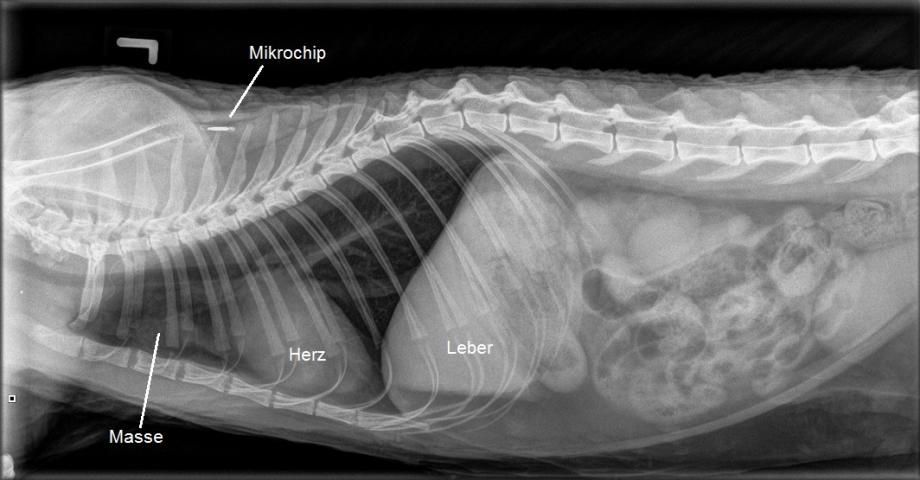

Eine Röntgenaufnahme des Brustkorbs von Nelson zeigt tatsächlich eine vor dem Herzen gelegene Masse. Genau in dieser Region liegt auch der Thymus - ein Organ, in dem beim Embryo und Welpen Abwehrzellen ausgebildet werden. Beim älterwerdenden Tier verschwindet der Thymus in aller Regel vollständig.

Eine Zelluntersuchung aus der Masse unterstützt den Verdacht, dass es sich hier um einen gutartigen Tumor des Thymus, ein Thymom handelt. Aufgrund ungeklärter Mechanismen können solche Geschwulste schwere Hautveränderungen verursachen, welche sich als die bei Nelson beobachtete Interface-Dermatitis manifestieren. Es handelt sich hier um ein sogenanntes paraneoplastisches Syndrom - hierunter werden alle Erscheinungen versammelt, welche eine direkte Folge einer Krebserkrankung darstellen. Weitere Beispiele von paraneoplastischen Syndromen sind beispielsweise Fieber, Blutarmut, erhöhte Blutcalcium-Werte sowie Abmagerung.